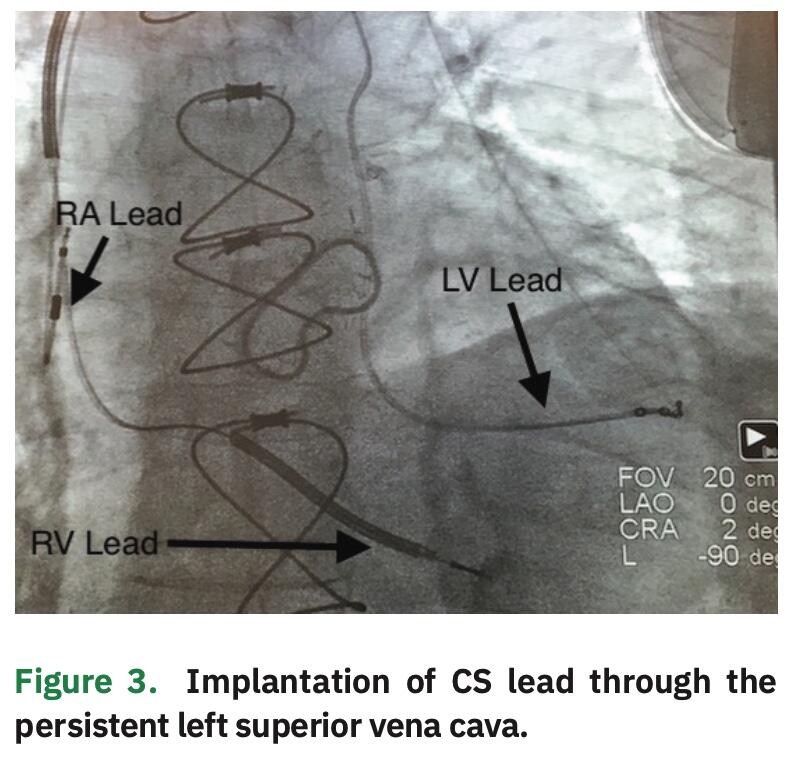

Given the subtotal occlusion, it was decided to abandon any further attempts of placement of the CS lead through the ostium. Rather, we proceeded with placement of the CS lead using the PLSVC. The previous venogram (Figure 1) demonstrated a medium to large caliber lateral vein without significant branching, which could be targeted with a quadripolar LV pacing lead. The inner catheter was utilized to subselect the PLSVC and deliver the lead into the lateral vein, which resulted in a stable lead position with adequate pacing and sensing characteristics. The greatest stability was achieved with the distal lead location within this vein. This site also provided an excellent pacing complex without diaphragmatic stimulation (Figure 4).